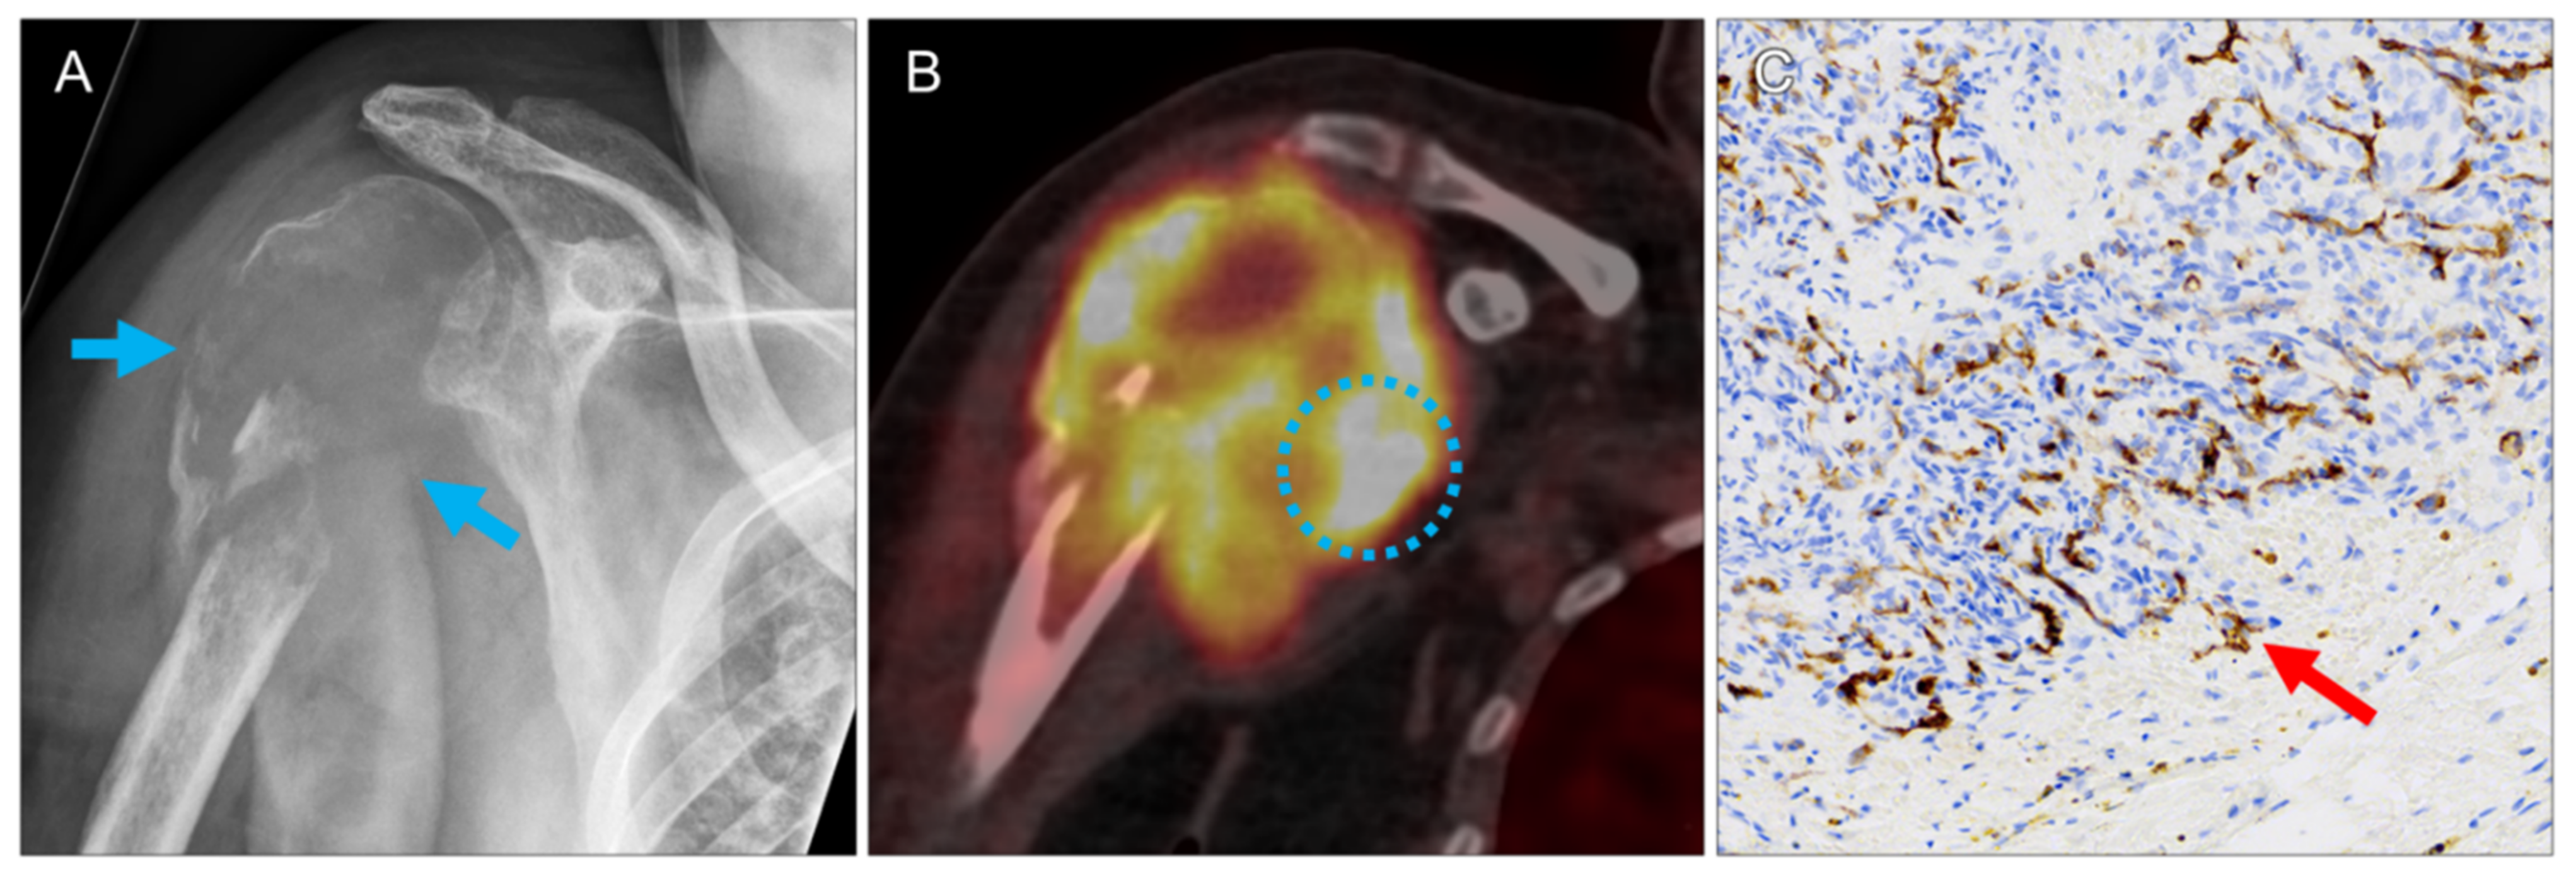

| 7 | right humerus | 8.1 | 15.2 | 23.4 | 13.7 | 26.0 | 3 | ccRCC | 3 | 2 | 4 | 3 |